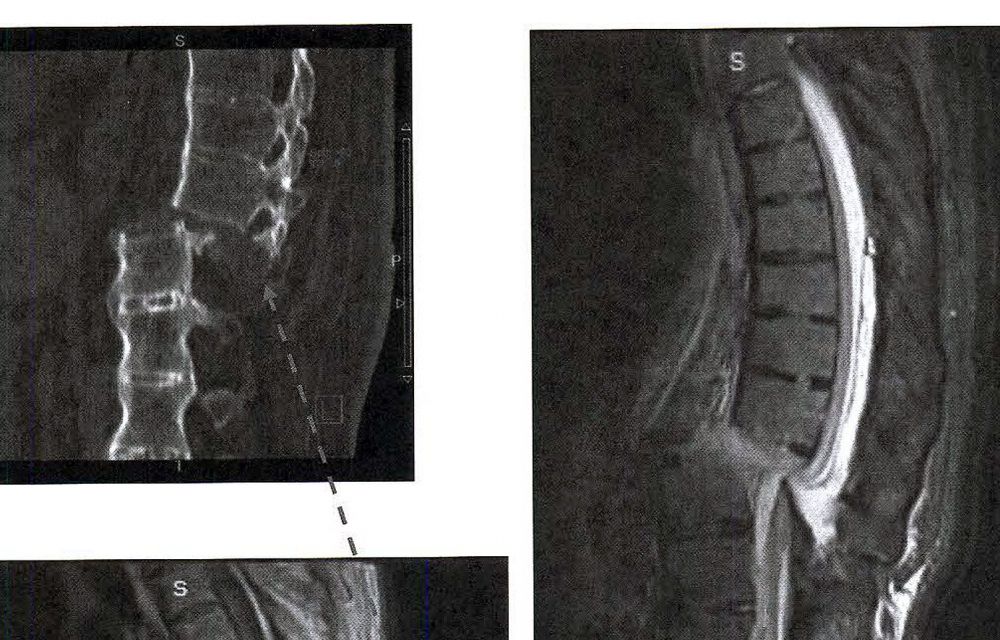

Les pericials encarregades indirectament per l’equip mèdic que va atendre l’home i per l’hospital de Meritxell ja estan d’acord amb l’informe sol·licitat per la part afectada en què “el dèficit neurològic” és molt probable que es produís “en el procés de transferència des del seu llit a la taula del quiròfan i/o en el posicionament del pacient en la posició quirúrgica necessària (decúbit pron) a la taula del quiròfan” però igual d’important com això seria “la malaltia degenerativa vertebral de base (l’espondilitis anquilopoiètica)” que patia la víctima i que hauria afavorit la lesió irreversible.

Entenen els experts contactats per l’asseguradora dels metges i l’hospital que la lesió soferta com a conseqüència de la caiguda esquiant ja hauria comportat els elements necessaris per acabar seccionant la columna. En paraules més planeres que les usades pels metges, mentre la massa muscular que subjecta la columna vertebral va estar tensada, l’esquelet va aguantar, però quan se’l va anestesiar per procedir a la intervenció quirúrgica la musculatura es va relaxar, va cedir, i això produir la ‘caiguda’ de l’ossamenta seccionar les vèrtebres. Recorden els informes de l’hospital que quan es va veure la gravetat de la lesió es va aturar d’immediat l’operació i es va decidir traslladar el pacient en una unitat especialitzada en lesions medul·lars, en aquest cas a la Vall d’Hebron.